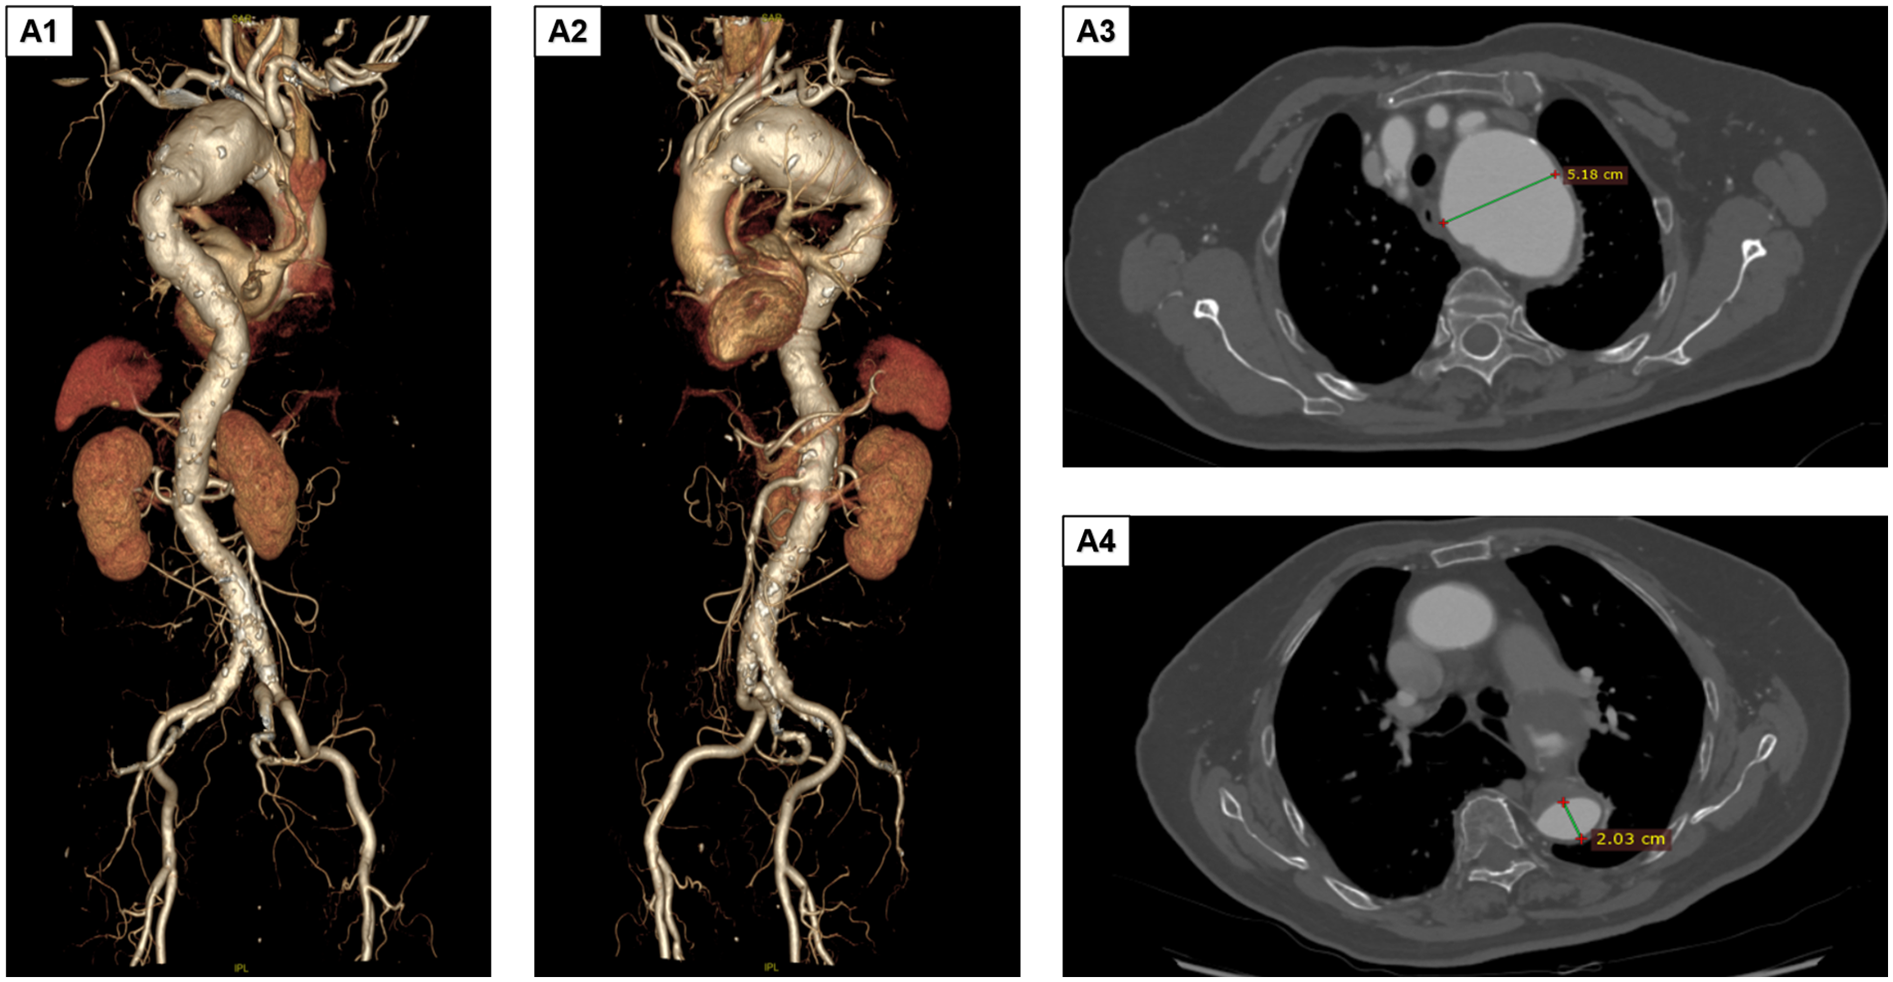

The patient was an 85-year-old woman who presented with aortic arch aneurysmal dilation discovered during a routine chest CT scan. She reported no clinical symptoms such as chest tightness or dyspnea. Her medical history included hypertension for 4 years (poorly controlled, with admission blood pressure of 161/85 mmHg) and type 2 diabetes for 2 years (random blood glucose level 10.1 mmol/L), with no other systemic diseases. Physical examination revealed no positive findings. Preoperative comprehensive evaluation identified multiple complex vascular pathologies, including lacunar cerebral infarction, moderate stenosis of the anterior and posterior cerebral arteries, vertebral artery stenosis, and atherosclerosis of the coronary and bilateral lower limb arteries. Preoperative digital subtraction angiography and computed tomography angiography (CTA) demonstrated a giant aortic arch aneurysm involving the left subclavian artery and extending into the thoracic aorta (approximately 9.0 × 5.1 cm, Figures 1A1,A2), aortic arch aneurysmal dilation (diameter 5.18 cm), and thoracic aortic aneurysmal dilation (diameter 2.03 cm, Figures 1A3,A4). Considering the patient's advanced age, complex vascular pathology, and high-risk profile for open surgery, TEVAR was selected following multidisciplinary team evaluation.

Figure 1

Preoperative DSA and CTA findings. (A1,A2) The aortic arch aneurysm involves the left subclavian artery and extends downward to the thoracic aorta. The size of the aneurysmal sac is approximately 9.0 × 5.1 cm. (A3,A4) The aortic arch shows aneurysmal dilation, with the maximum diameter measuring approximately a5.18 cm. Additionally, aneurysmal dilation of the thoracic aorta is observed, with a diameter of approximately 2.03 cm. DSA, digital subtraction angiography; CTA, computed tomography angiography.